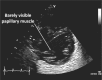

Cardiac ultrasound techniques are increasingly used in the neonatal intensive care unit to guide cardiorespiratory care of the sick newborn. This is the first in a series of eight review articles discussing the current status of "neonatologist-performed echocardiography" (NPE). The aim of this introductory review is to discuss four key elements of NPE. Indications for scanning are summarized to give the neonatologist with echocardiography skills a clear scope of practice. The fundamental physics of ultrasound are explained to allow for image optimization and avoid erroneous conclusions from artifacts. To ensure patient safety during echocardiography recommendations are given to prevent cardiorespiratory instability, hypothermia, infection, and skin lesions. A structured approach to echocardiography, with the same standard views acquired in the same sequence at each scan, is suggested in order to ensure that the neonatologist confirms normal structural anatomy or acquires the necessary images for a pediatric cardiologist to do so when reviewing the scan.